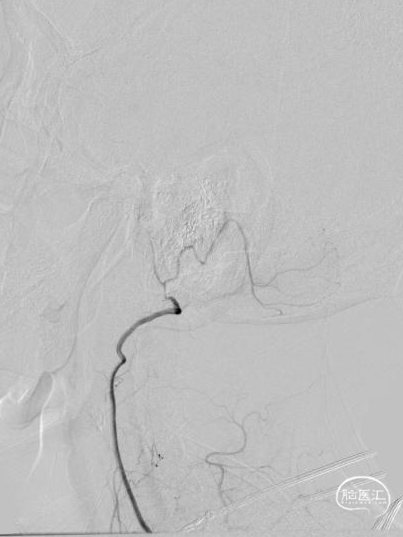

03 手术过程

➢术后即刻影像

为减少血栓逃逸事件的发生及对椎动脉血管的刺激,我们选取了预留中间管+Syphonet®取栓支架作SWIM取栓准备。这款支架全程显影,且头端带网篮,对球囊扩张过程中的逃逸血栓有抓捕能力,且抗折性强,迂曲血管内能保持完整管腔,内置的支架输送导丝头端柔软可避免血管损伤,在该病例中发挥了保护伞的作用。